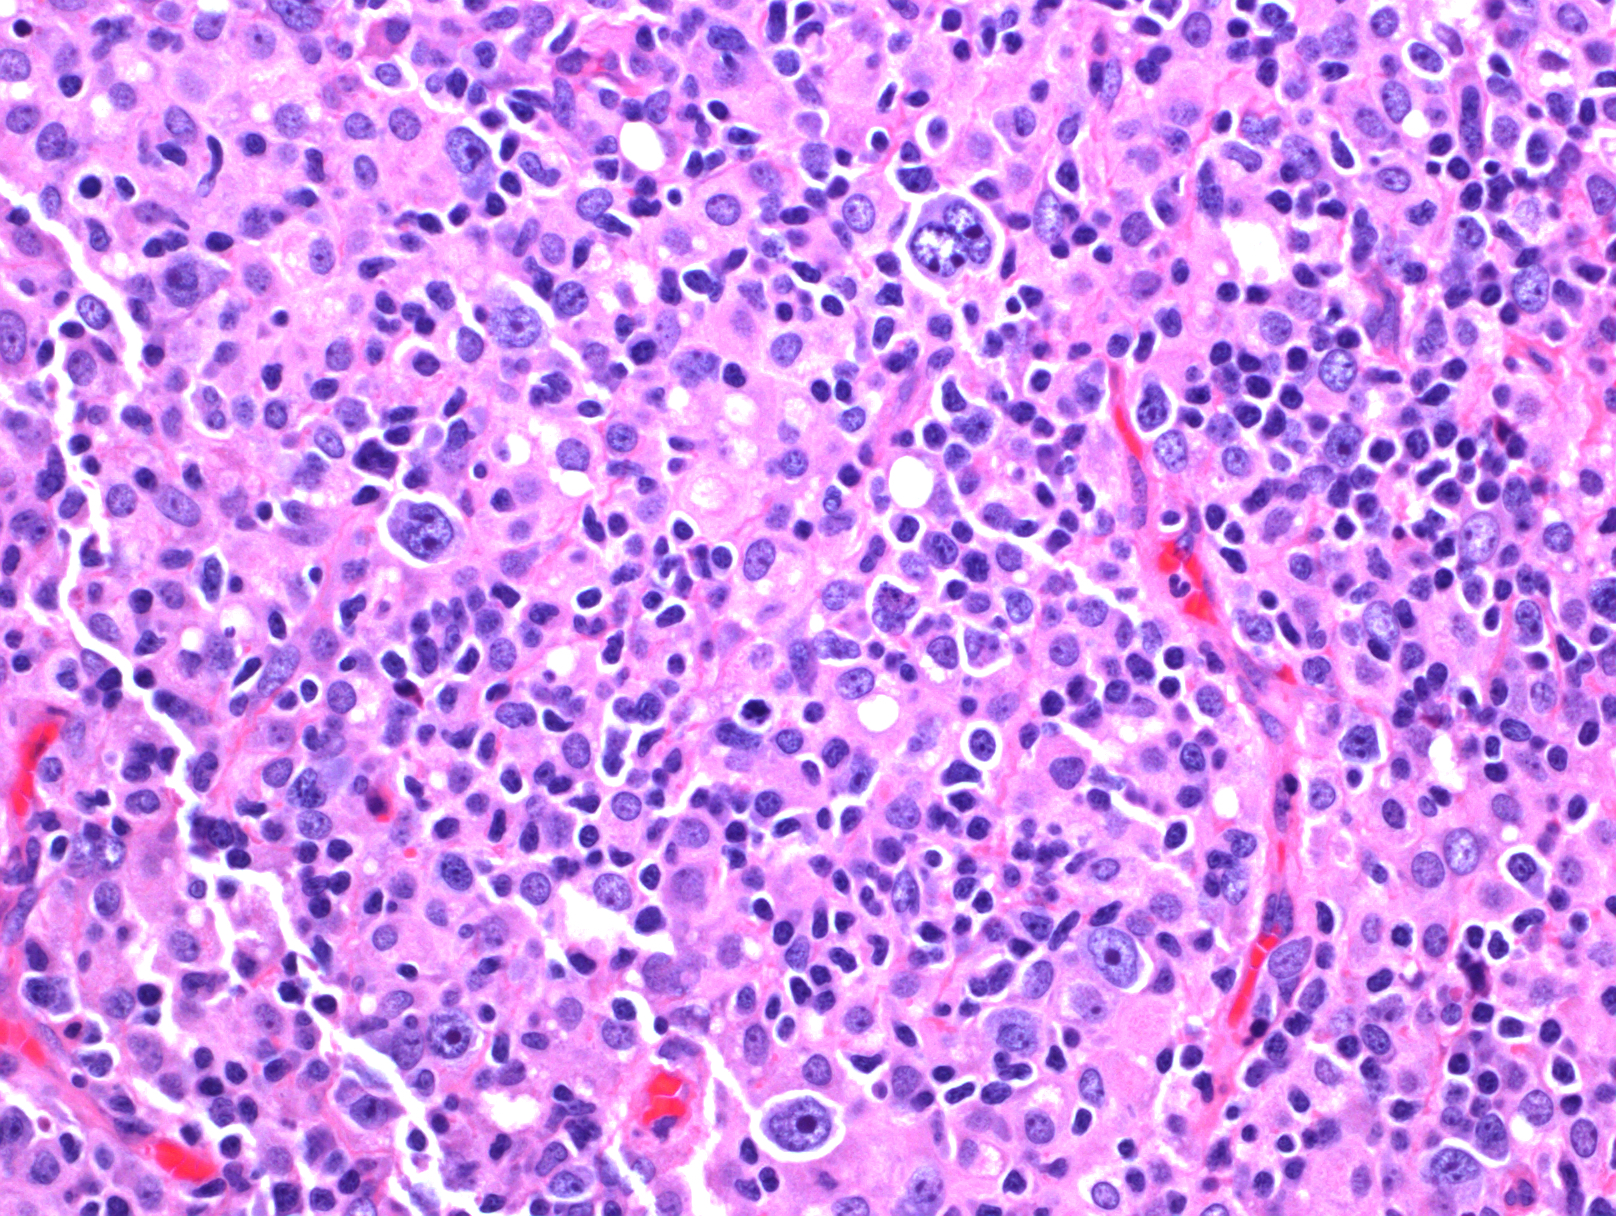

- 肿瘤细胞弥漫浸润,正常组织或淋巴结结构完全破坏,常伴凝固性坏死。

- 肿瘤细胞型态类似中心母细胞、免疫母细胞,浆母细胞、Reed-Sternberg 样细胞或呈现多形性细胞。老年多累及结外组织,常表现两种形态亚型:(1)多形态亚型:肿瘤细胞中混有大量反应性细胞如小淋巴细胞、组织细胞和浆细胞;(2)大细胞亚型:成片大肿瘤细胞。年轻人多累及淋巴结,常表现为三种形态亚型:(1)T/组织细胞丰富型大 B 细胞淋巴瘤样;(2)灰区淋巴瘤样(介于典型霍奇金淋巴瘤和弥漫大 B 淋巴瘤之间);(3)弥漫大 B 淋巴瘤(非特指)样。以上亚型的确定虽有助诊断,但有一定主观随意性,不是必需的。